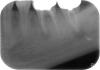

esto4ka Опубликовано 12 января, 2013 Автор Поделиться Опубликовано 12 января, 2013 И вот еще у меня два вопроса.1,Врач, резецируя 7 сказал,что канал изогнут в сторону языка(анатомическая особенность)и что материал по этой причине он заложить не смог.Разъясните неграмотной.Как это возможно?И насколько это чревато?Прилагаю фото до резекции.И второй вопрос.Как я понимаю на 6 есть межкорневое разрежение.Означает ли это,что резекцией уже и этому зубу не помочь? Ссылка на комментарий

esto4ka Опубликовано 18 января, 2013 Автор Поделиться Опубликовано 18 января, 2013 Выставляю,обещанный снимок после резекции.Правда сделан он в день резекции,как контроль перед окончанием процедуры.Не знаю,сможет ли он вам что-либо сказать,господа Доктора? Ссылка на комментарий

kriokov Опубликовано 18 января, 2013 Поделиться Опубликовано 18 января, 2013 Выставляю,обещанный снимок после резекции.Правда сделан он в день резекции,как контроль перед окончанием процедуры.Не знаю,сможет ли он вам что-либо сказать,господа Доктора?по снимку выполнено "запечатывание верхушек" ретроградно, из раны, У Вас ощущение выросшего зуба прошло, жуете? Ссылка на комментарий

kriokov Опубликовано 18 января, 2013 Поделиться Опубликовано 18 января, 2013 Да,Доктор -ощущение прошло,жевать пока не жую,боюсь.Или уже можно?Как там с костной тканью дела обстоят?А что это значит для меня?Ретроградно, из раны.ретроградно--т.е каналы зубов в обл верхушек корней пломбировали во время операциина счет жевания-- лучше с доктором своим посоветоваться, думаю можно.Костные дефекты небольшие, если операция прошла успешно, кость восстановиться Ссылка на комментарий